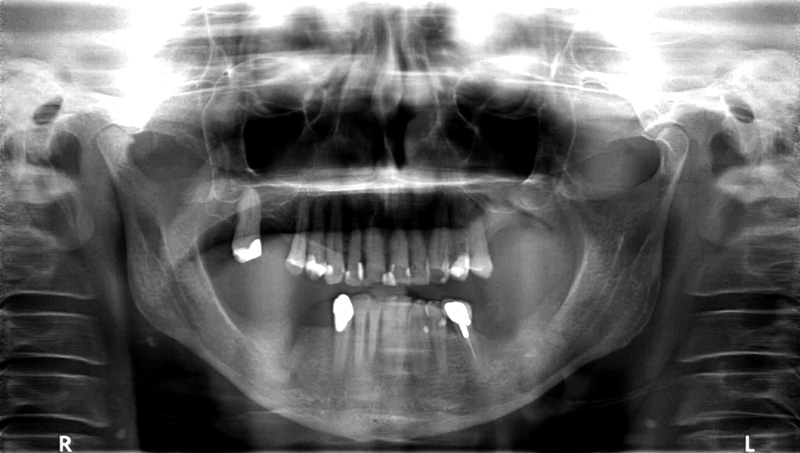

01/14 - Free-end situation in right mandible

Block augmentation with maxgraft® in the mandible - PD Dr. Dr. F. Kloss

02/14 - Preoperative radiological situation